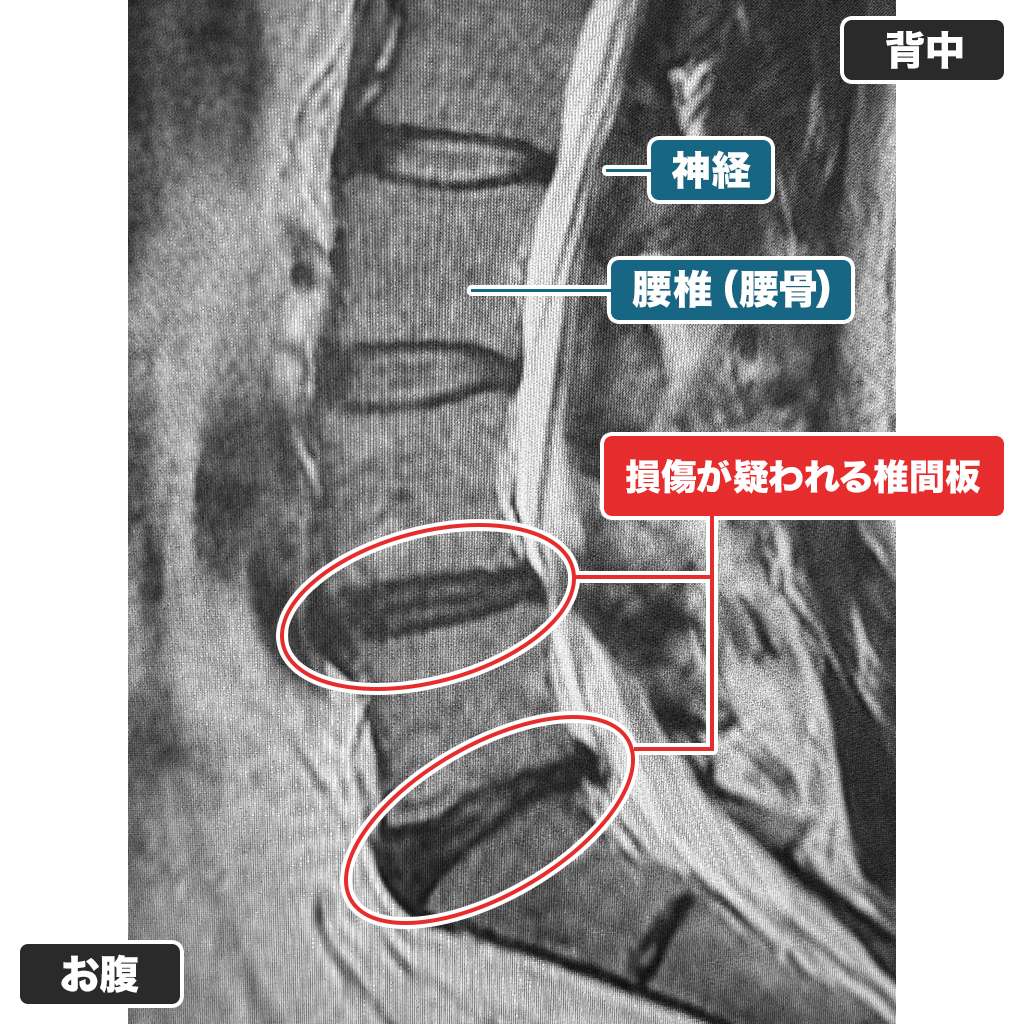

MRI

腰のMRI検査です。L4/5、L5/Sの椎間板ヘルニアを認めます。椎間板容量は減少傾向であり、繊維輪損傷が疑われます。北米での画像診断でも同様の内容であったそうです。